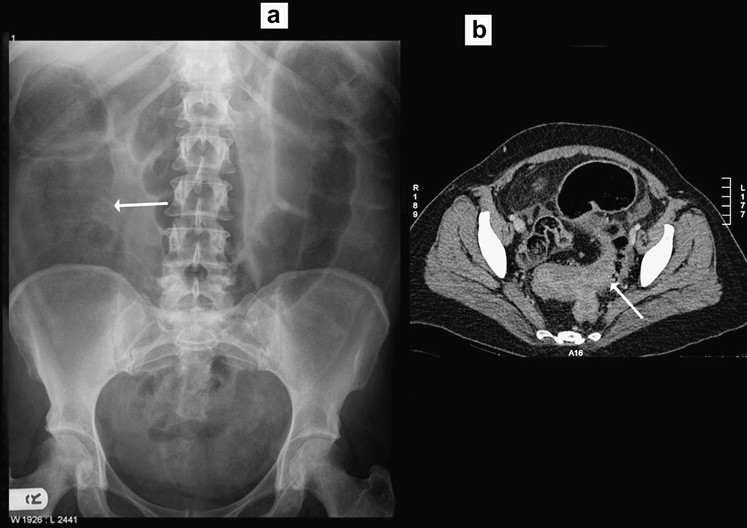

Xoắn xảy ra khi đại tràng sigma xoắn mạc treo của nó gây tắc ruột quai đóng (closed loop obstruction). Các bệnh nhân có thể có các triệu chứng đau bụng cấp hoặc âm ỉ tùy thuộc vào tình trạng xoắn gây tắc hoàn toàn hoặc bán phần. Trên phim X quang bụng, quai đại tràng sigma giãn to (không còn ngấn ngang) nhô lên khỏi tiểu khung và kéo cao đến phần trên của ổ bụng, thường lệch sang phải. Hình ảnh này được gọi là dấu hiệu “hạt cà phê” (Hình 4).

Hình 4. Xoắn đại tràng sigma (a) Phim X quang bụng thấy đại tràng sigma giãn to nhô từ tiểu khung lên ổ bụng (hình “hạt cà phê”) sát với đại tràng ngang. (b, c) Chụp CT xác định xoắn đại tràng sigma. Lưu ý dấu hiệu “mỏ chim” của mạc treo đại tràng sigma bị xoắn.

Xoắn manh tràng ít xảy ra so với xoắn đại tràng sigma, chỉ chiếm dưới 5% các trường hợp tắc đại tràng. Xoắn thường ở những người trung niên, điển hình là những người không có tiền sử phẫu thuật ổ bụng. Xoắn ở đại tràng lên, vị trí điển hình là ngay trên van hồi-manh tràng. Phim X quang bụng thường cho phép chẩn đoán và cho thấy quai ruột giãn to kéo từ hố chậu phải đến góc phần tư trên trái ổ bụng. Ruột non thường giãn và đại tràng ở đầu xa bị xẹp. Chụp cắt lớp vi tính hiếm khi được yêu cầu để khẳng định chẩn đoán, nhưng mục đích để phát hiện mạc treo bị xoắn và đoạn ruột bị thiếu máu hoặc thủng (Hình 5).

Hình 5. Xoắn manh tràng (a) Phim X quang bụng đứng thấy một quai ruột giãn nhô vào góc trên trái ổ bụng. Lưu y không có khí trong các đoạn đại tràng, các quai ruột non giãn to (b, c) Chụp CT xác định xoắn manh tràng, cũng thấy hình “mỏ chim” của mạc treo manh tràng xoắn.